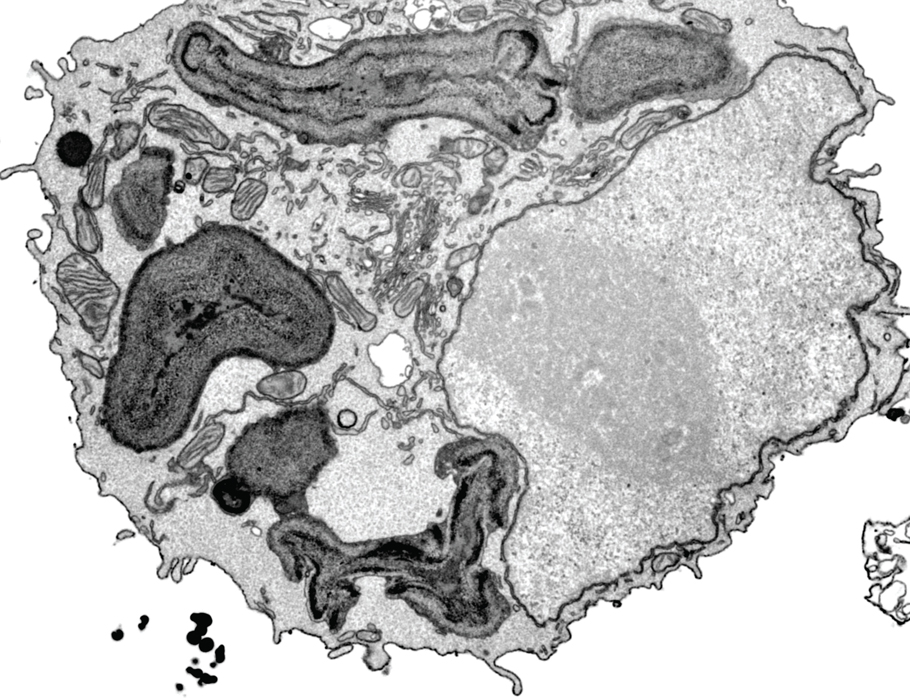

New research in Science #Immunology identifies the pore-forming protein #APOL7C as a driver of phagosomal rupture and antigen cross-presentation in activated dendritic cells. Johnathan Canton Gerone Gonzales Liam Wilkinson Cassie Wood bit.ly/3CjeKWp

A new Science #Immunology study describes how #APOL7C recruitment to phagosome membranes in conventional #DendriticCells promotes antigen release to the cytosol and cross-presentation. @ucalgaryvetmed U Calgary bit.ly/3CjeKWp